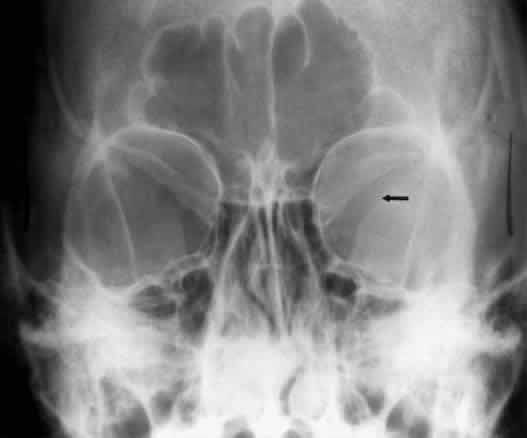

CALDWELL PROJECTION

In 1918 the evaluation of the frontal and ethmoid sinuses prompted Caldwell9 to describe a projection (Fig. 3) that eliminates the superimposition of the sphenoid bone on these paranasal sinuses. The patient is positioned with both the nose and forehead against the x-ray cassette while the x-ray beam is directed downward 15 degrees to 23 degrees to the canthomeatal line.5,6,9 This orientation also projects the petrous bones inferior to the orbit, thus avoiding obscuration of the orbital structures. As in the Waters view, the Caldwell view is a posterior-anterior projection. This excellent view of the frontal and ethmoid sinuses also allows good visualization of the orbital rims, greater and lesser sphenoid wings, lacrimal gland fossa, medial orbital wall, and both the superior and inferior orbital fissures.10 The innominate line is prominent in this view and represents the depression on the temporal surface of the greater wing of the sphenoid bone where it forms the medial wall of the temporal fossa or lateral wall of the orbit. This innominate line can be straight, end with a medial right angle turn, or continue inferiorly to form the outline of the pterygoid plate.8 A lack of continuity of the innominate line suggests a fracture of the lateral orbital wall.

Fig. 3. A. Schematic showing positioning for a Caldwell projection. (CM, canthomeatal line; CR, central ray) B. Radiograph of a Caldwell projection. The petrous ridge is positioned at the orbital floor. Detail of the orbital floor and maxillary sinus is blocked. C. The radiograph is taken at a steeper angle so the petrous ridge is now positioned lower within the maxillary antrum. (a, frontal sinus; b, innominate line; c, inferior orbital rim; d, posterior orbital floor; e, superior orbital fissure; f, greater wing of sphenoid;g, ethmoid sinus; h, medial orbital wall; i, petrous ridge; j, zygomatic-frontal suture; k, foramen rotundum) (A; Rao VM, Gonzalez CF: Plain film radiography and polytomography of the orbit. In Gonzalez CF, Becker MH, Flanagan JC [eds]: Diagnostic Imaging in Ophthalmology, pp 1–7. New York, Springer Verlag, 1986)

The posterior segment of the lateral wall courses posterior medially and can be seen in anterior projections such as the Caldwell view. This view allows direct visualization of the greater sphenoid wing contribution to the lateral wall. Bone density changes in the greater wing of the sphenoid, such as from a meningioma, can be detected. Fractures of the lateral orbital wall can occur from blunt trauma to the malar prominence. The zygomatic complex fracture (tripod) results from separation of the zygomatic-frontal, zygomatic-temporal, and the zygomatic-maxillary sutures. These fractures are associated with an inferior displacement of the malar prominence and a rounded lateral canthus (Figs. 8 and 9).

Fig. 8. A zygomatic complex fracture (tripod) after blunt trauma to the right cheek. Note the right zygoma is inferiorly displaced. (a, zygomatic-frontal suture separation; b, orbital rim disruption; c, opacification of maxillary sinus)